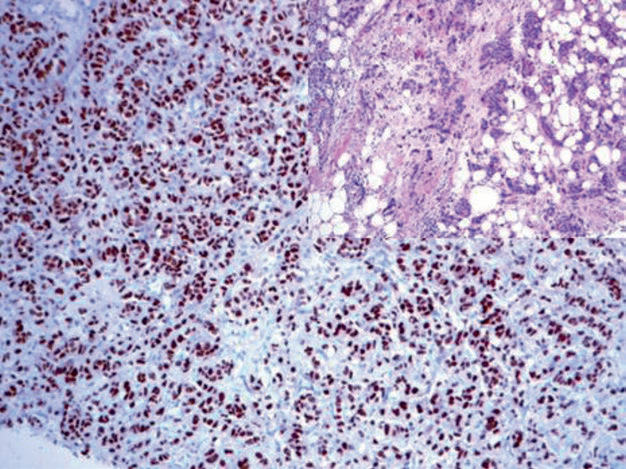

图1. 乳腺癌,ER在细胞核强阳性表达。

图3. 乳腺浸润性导管癌,骨转移灶;免疫组化肿瘤细胞的细胞核强阳性表达GATA-3。